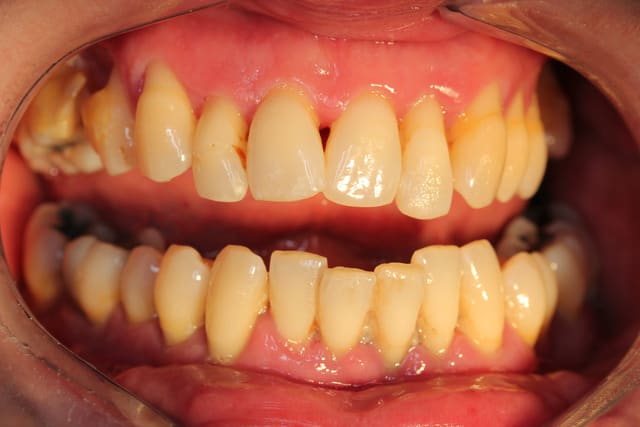

1.Bon... situation pré-extractionelle ( Je crois qu il faillait vraiment extraire )

2. Complet à essai en bouche après extraction et PRFs ds tous les alvéoles puis 3 séances d ostéotensions à venir pour le maxillaire

3. Vue sur articu

4. Télé de profil post-extractionelle

Bon la suite sera ostéotension mandibule et pose des implants mandibulaires en enfoui ds 45 j

Ensuite qd on aura les dents provisoires du bas on sera à peu près prêt pour scan du haut et materialise